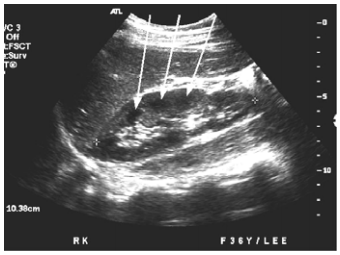

60 附圖是一名 11 個月大嬰兒右上腹部之橫向掃描,箭號所指的病變最可能是:

(A)胃癌 (B)腸套疊 (C)結腸淋巴癌(lymphoma) (D)闌尾炎